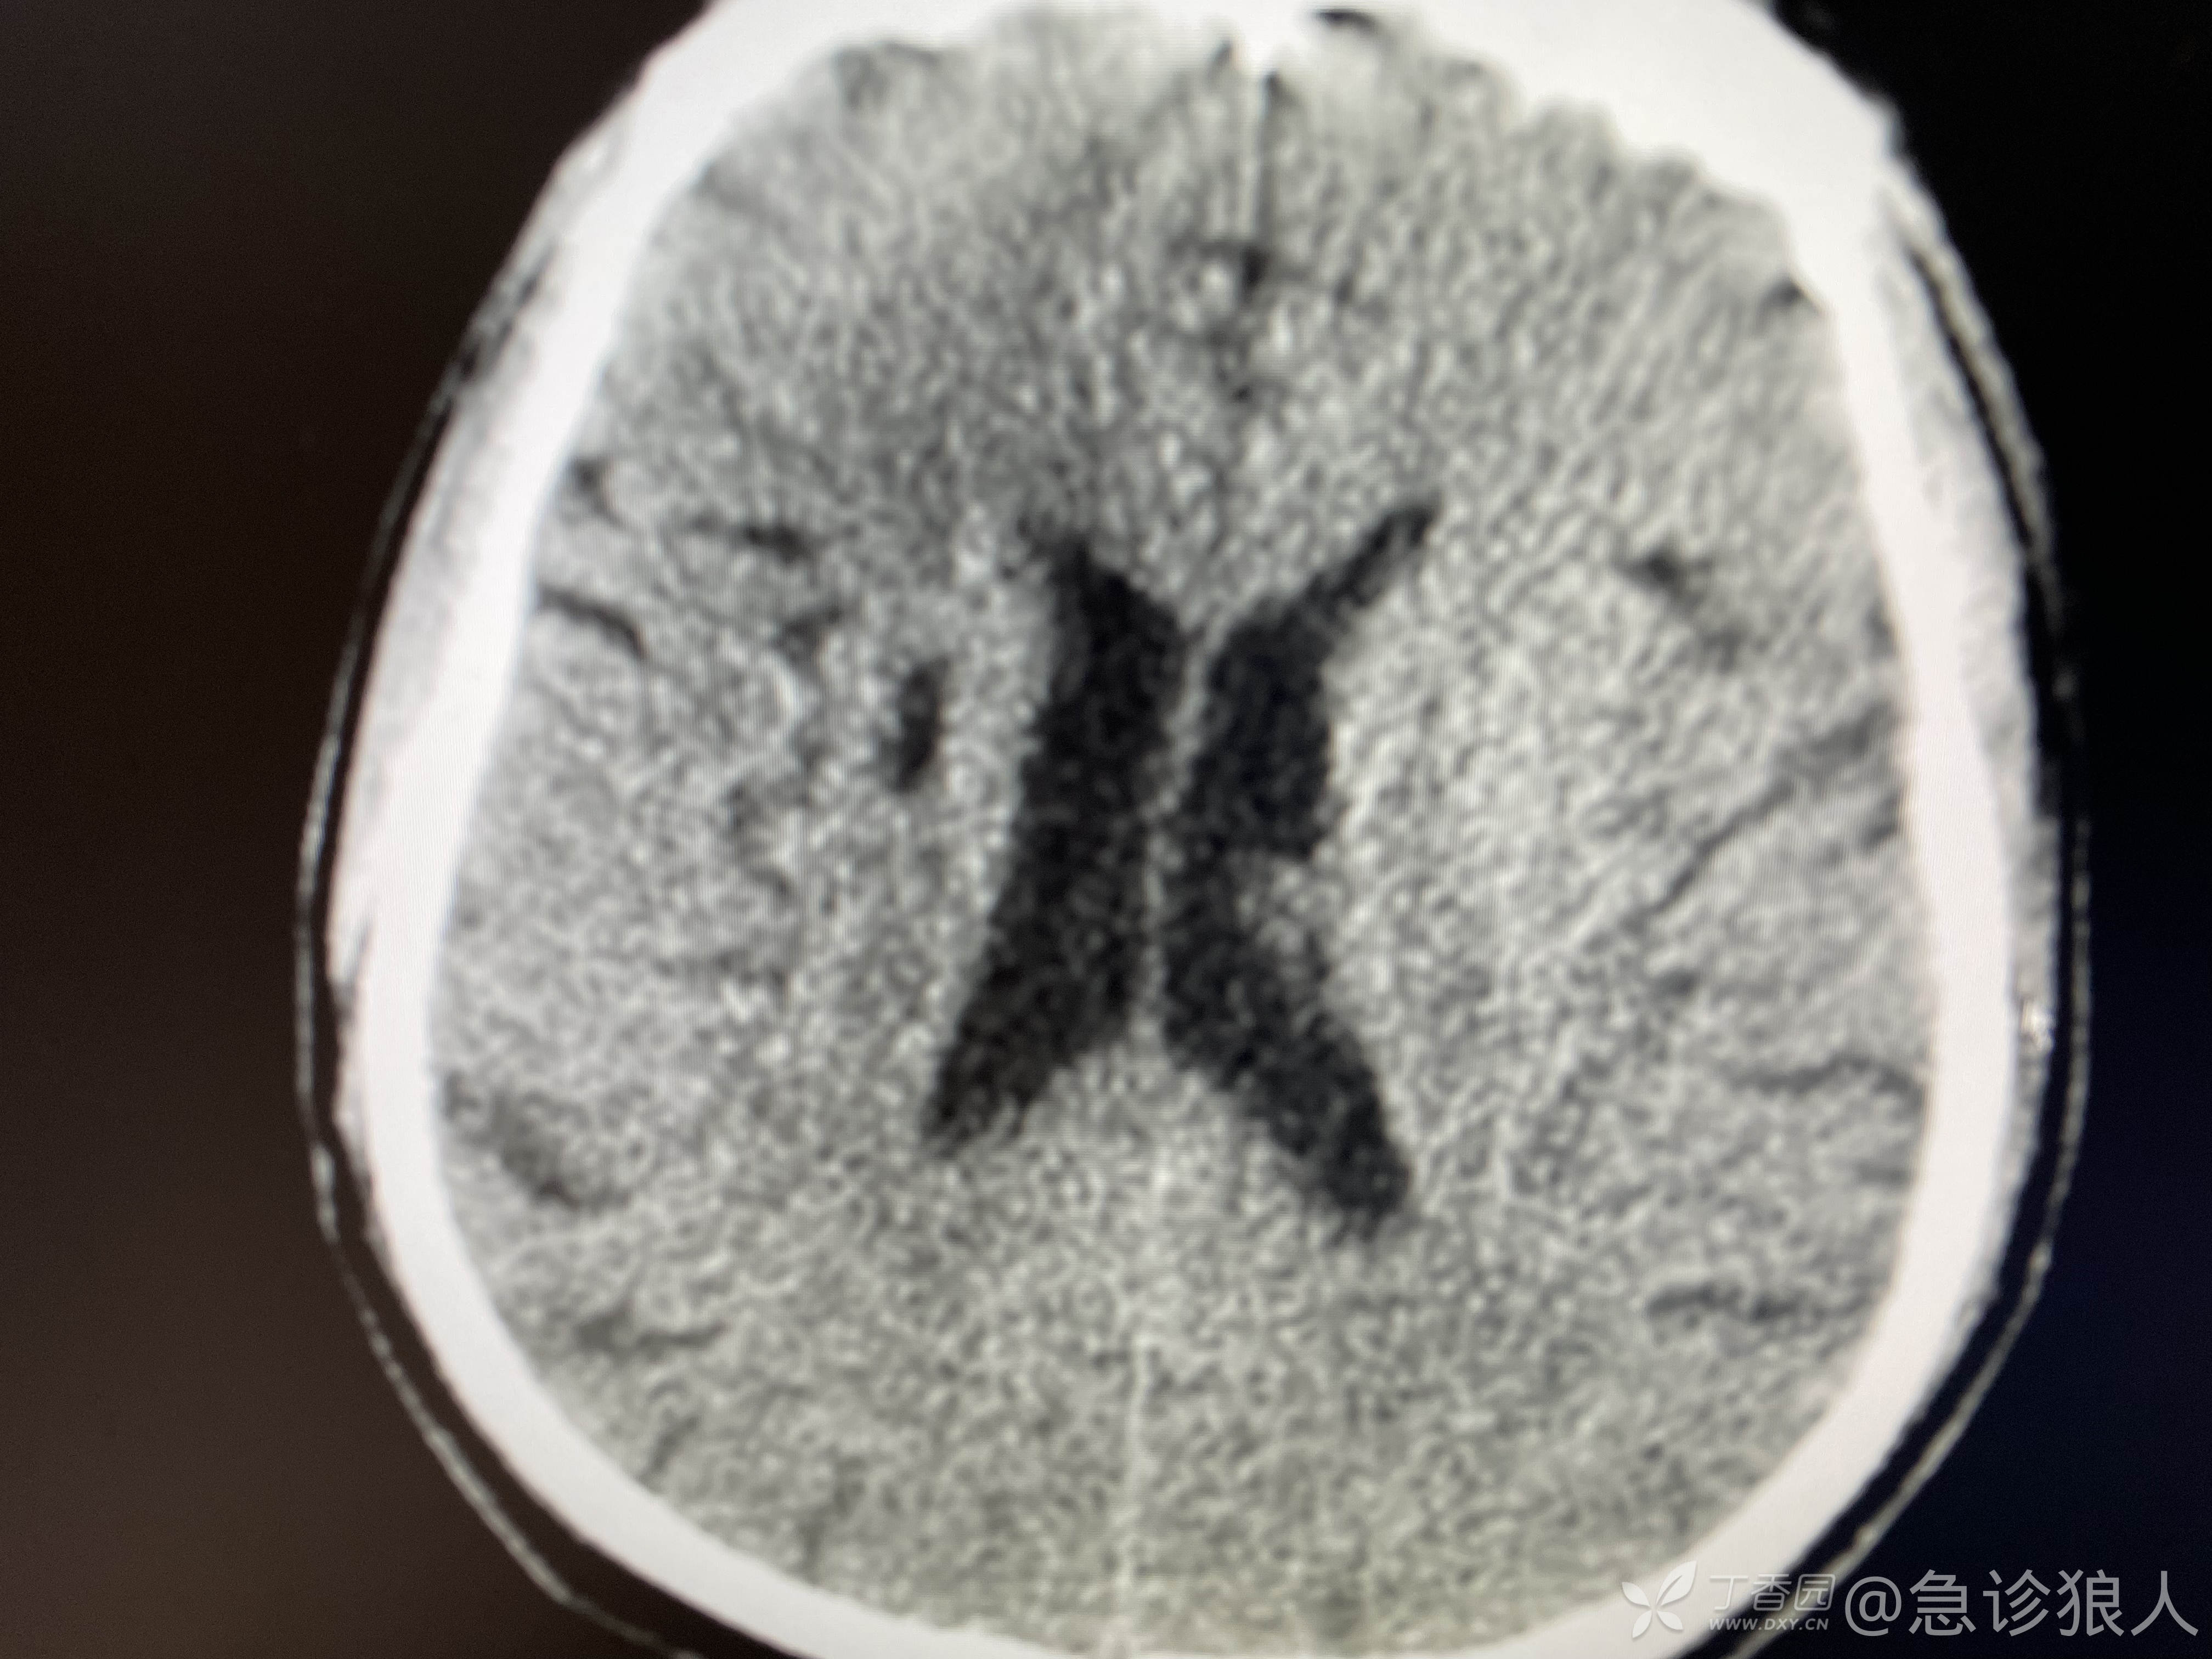

可是ct如下:

看完ct,什么感觉?

脑内软化灶,有点时间了,肾周渗出,可能是新的!